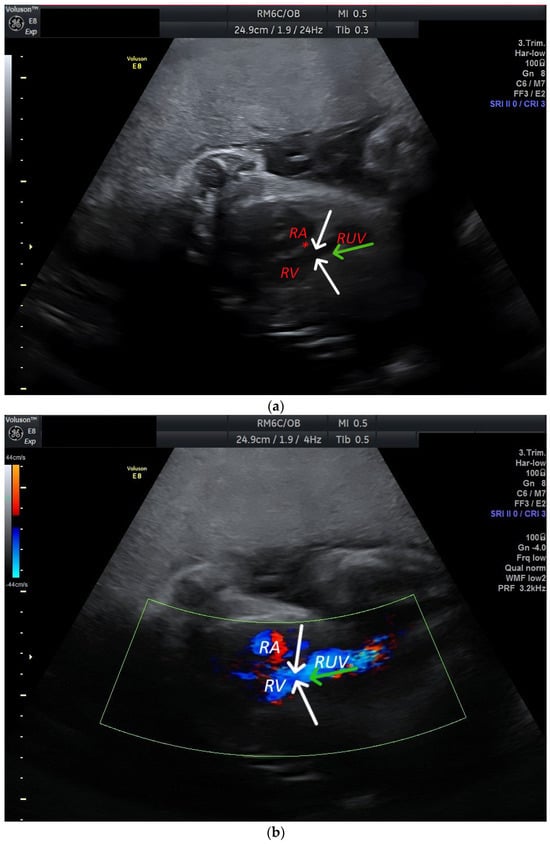

| RA | Right atrium |

| RV | Right ventricle |

| RUV | Right umbilical vein |